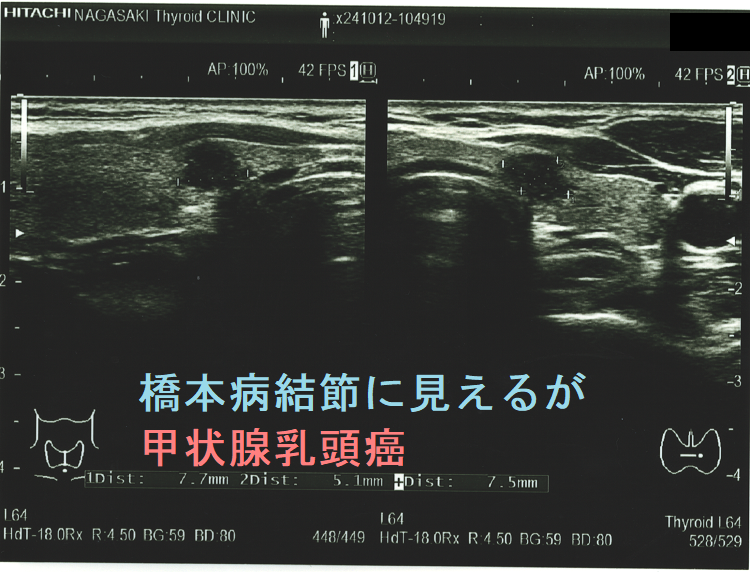

ケース① どう見ても腺腫様結節、しかし甲状腺乳頭癌

逆に、甲状腺乳頭癌に見えるが腺腫様結節の場合もあります。